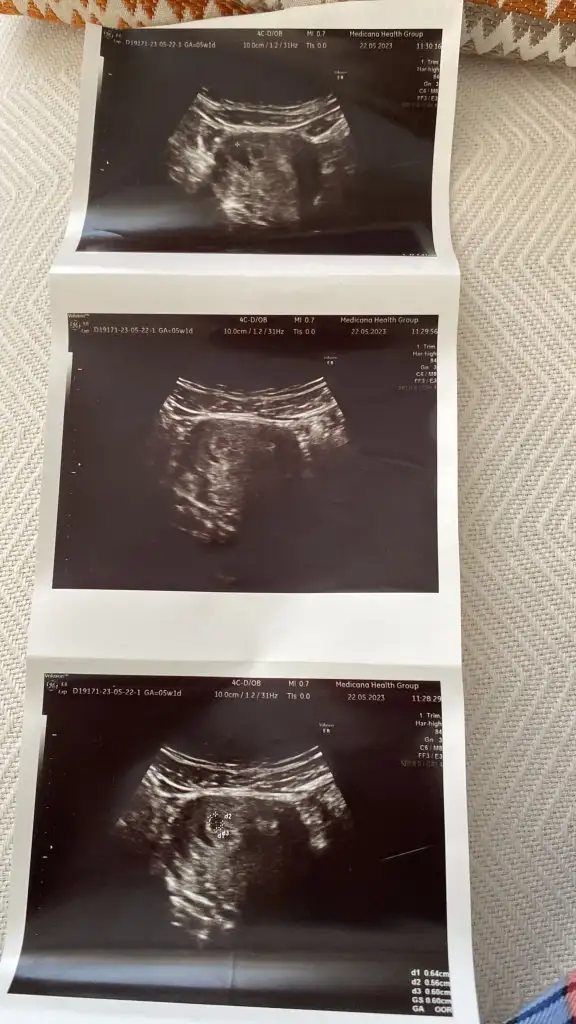

Karından usg lerde ayna etkisi yaratabiliyor. Sağı solda solu sağda gösterebiliyor. En doğrusu vajinal usgler. Vajinale göre solda bu bebiş kızmelegim can canımm bu bebiş vajınalde gecen haftaya gore diğer tarafta gozukuyo bu sefer kıza mı dondu acaba